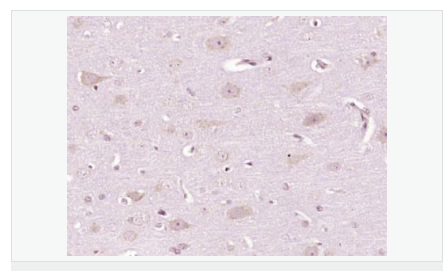

| 產(chǎn)品應用 | WB=1:500-2000 IHC-P=1:100-500 IHC-F=1:100-500 ICC=1:100-500 IF=1:100-500 (石蠟切片需做抗原修復) not yet tested in other applications. optimal dilutions/concentrations should be determined by the end user. |